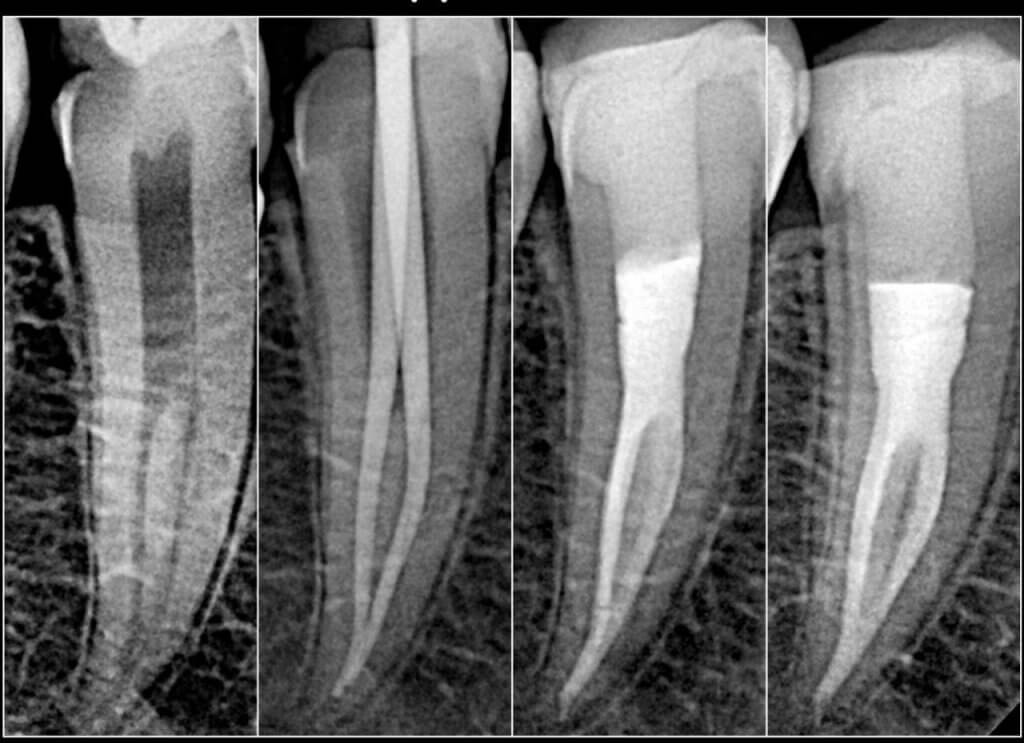

علاج جذور الأسنان هو إجراء يهدف إلى:

- إزالة الجزء المصاب أو التالف داخل السن.

- تنظيف داخل السن.

- إغلاقه (حشوه) للحفاظ على صحته.

- ترميم السن بحشوة ثم وضع تاج (كراون).